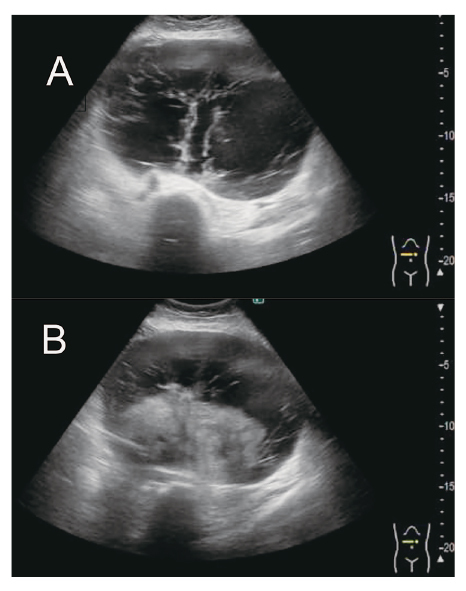

Uterine leiomyomas, benign tumors common in reproductive-aged women, can display rare variants such as hydropic leiomyoma (HL), which exhibit unique histological features like zonal edema and increased vascularity. However, due to its rarity, comprehensive clinical knowledge about HL is limited. We report a case of a 49-year-old Japanese woman who was premenopausal and nulliparous, presenting with a two-year history of abdominal distension. An MRI scan revealed a 20 cm mass in the posterior part of the uterus, exhibiting characteristics suggestive of an ovarian tumor. During laparotomy, a cystic tumor connected with a swollen fibroid was found, and pathology confirmed HL. This case emphasizes that hydropic leiomyomas can mimic malignant tumors on ultrasonography due to their atypical features, necessitating additional evaluations using alternative imaging techniques or histopathological examinations for accurate diagnosis and appropriate management. The patient recovered uneventfully, broadening our understanding of HL's clinical presentation.